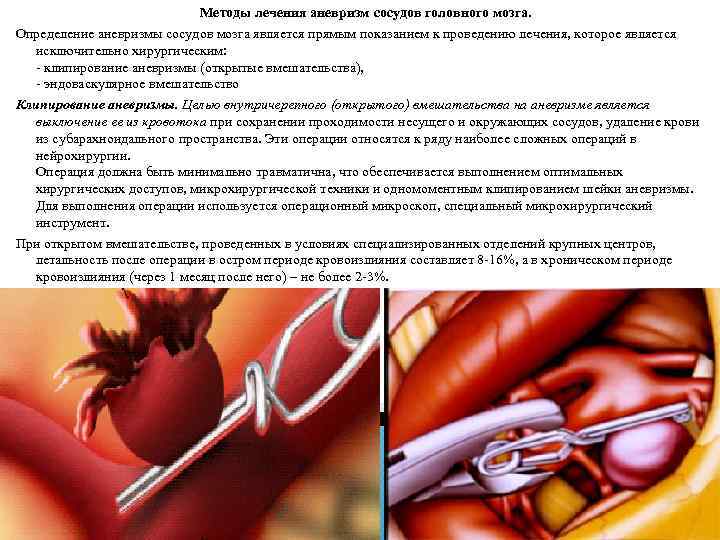

Методы лечения аневризм сосудов головного мозга. Определение аневризмы сосудов мозга является прямым показанием к проведению лечения, которое является исключительно хирургическим: - клипирование аневризмы (открытые вмешательства), - эндоваскулярное вмешательство Клипирование аневризмы. Целью внутричерепного (открытого) вмешательства на аневризме является выключение ее из кровотока при сохранении проходимости несущего и окружающих сосудов, удаление крови из субарахноидального пространства. Эти операции относятся к ряду наиболее сложных операций в нейрохирургии. Операция должна быть минимально травматична, что обеспечивается выполнением оптимальных хирургических доступов, микрохирургической техники и одномоментным клипированием шейки аневризмы. Для выполнения операции используется операционный микроскоп, специальный микрохирургический инструмент. При открытом вмешательстве, проведенных в условиях специализированных отделений крупных центров, летальность после операции в остром периоде кровоизлияния составляет 8 -16%, а в хроническом периоде кровоизлияния (через 1 месяц после него) – не более 2 -3%.

Интраоперационная фотография. Двухкамерная аневризма развилки средней мозговой артерии. Аневризма клипирована, клипс лежит на шейке аневризмы.